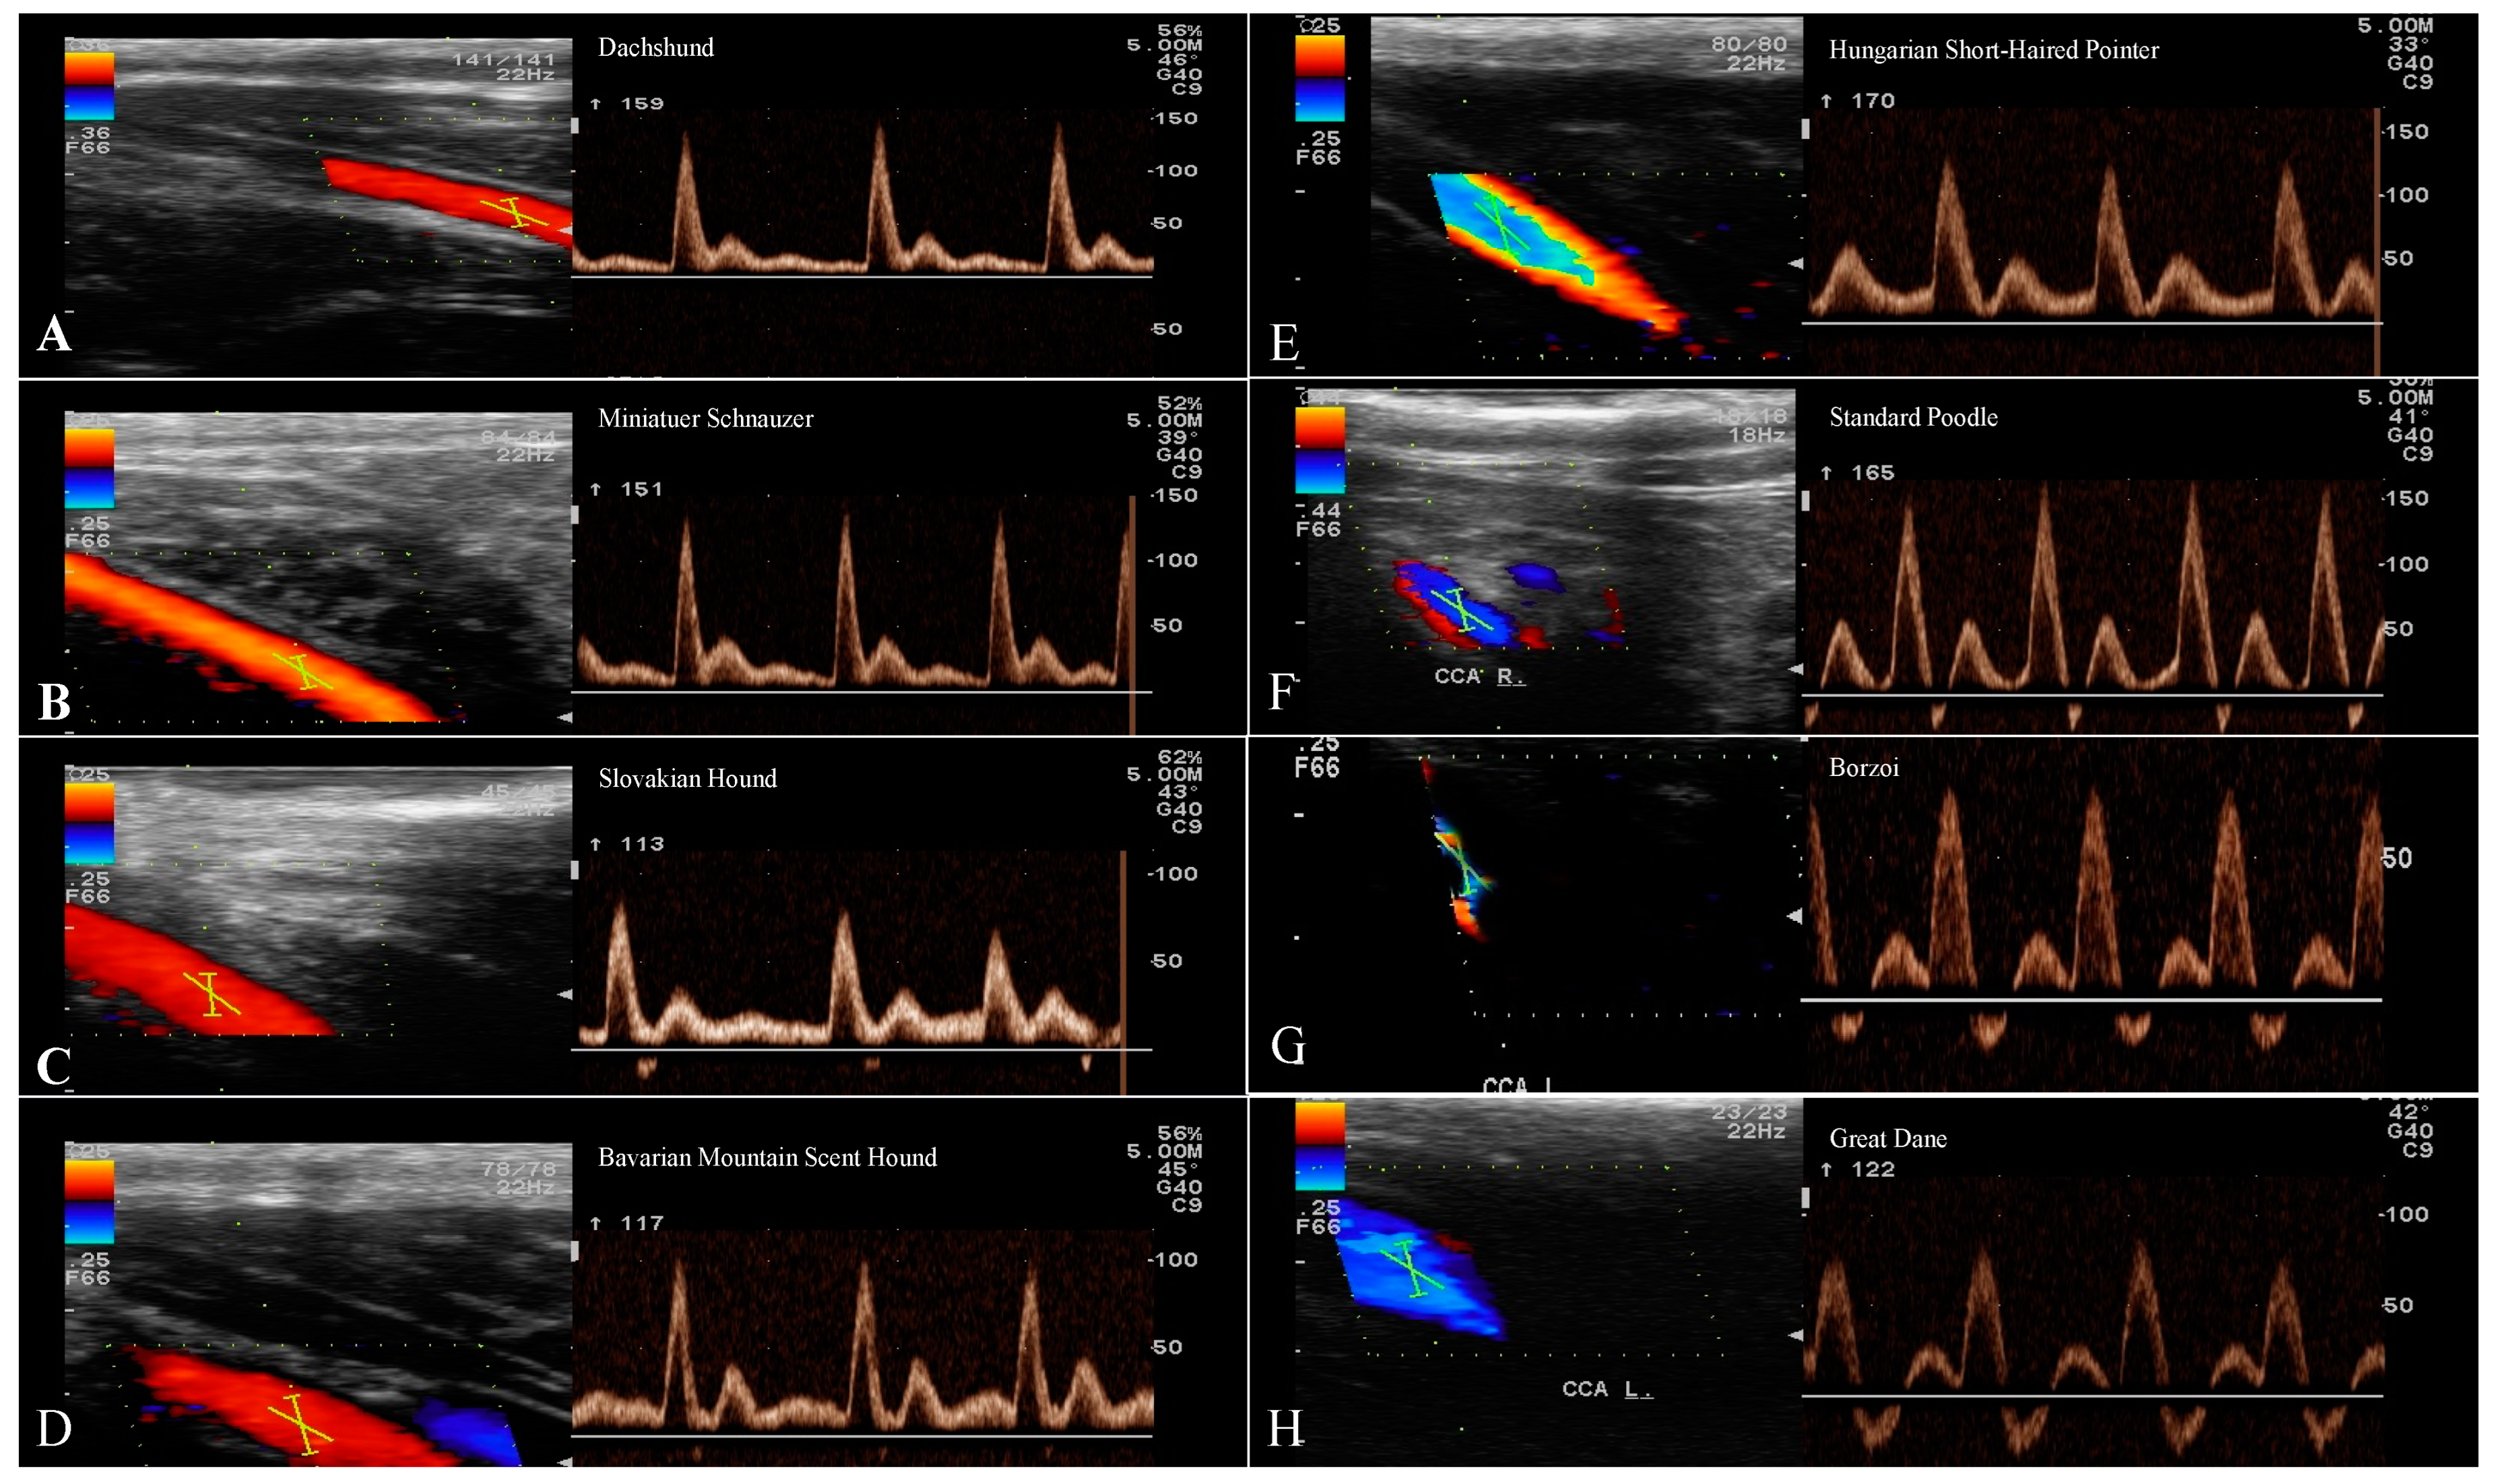

3.3. Evaluation of the CCA

| CCA | |||||||

|---|---|---|---|---|---|---|---|

| n | Ø (mm) | RI | PSV (cm/s) | EDV (cm/s) | S/D | ||

| Small breeds | Dachshund | 13 | 2.5 | 0.84 | 130.6 ± 15.56 | 17.98 ± 4.48 | 7.84 ± 2.1 |

| Miniature Schnauzer | 13 | 2.3 | 0.84 | 127.3 ± 13.49 | 19.57 ± 3.68 | 6.85 ± 1.7 | |

| Medium breeds | Slovakian Hound | 13 | 3.5 | 0.81 | 108.1 ± 17.39 | 19.96 ± 6.83 | 6.47 ± 2.9 |

| Bavarian Mountain Scent Hound | 13 | 3.6 | 0.76 | 115.4 ± 21.7 | 30.71 ± 7.1 | 3.88 ± 0.4 | |

| Large breeds | Hungarian Short-Haired Pointer | 13 | 3.5 | 0.76 | 119.9 ± 16.07 | 27.52 ± 5.63 | 4.63 ± 0.98 |

| Standard Poodle | 13 | 3.5 | 0.79 | 106.7 ± 9.2 | 22.31 ± 4.49 | 5 ± 0.77 | |

| Giant breeds | Borzoi | 13 | 3.2 | 0.78 | 96.54 ± 6.21 | 22.3 ± 1.56 | 4.49 ± 0.54 |

| Great Dane | 13 | 5.7 | 0.66 | 94.37 ± 18.7 | 31.43 ± 12 | 3.40 ± 0.95 | |